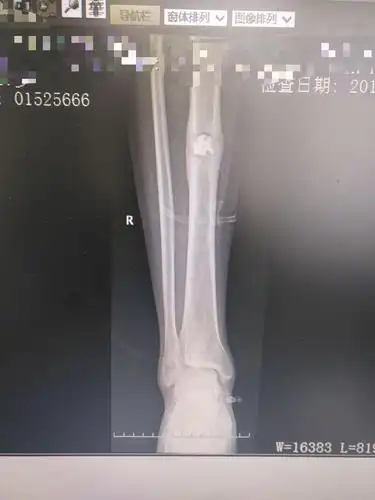

胫骨慢性骨髓炎

左胫骨慢性骨髓炎

这一例胫骨慢性骨髓炎大家有啥好建议